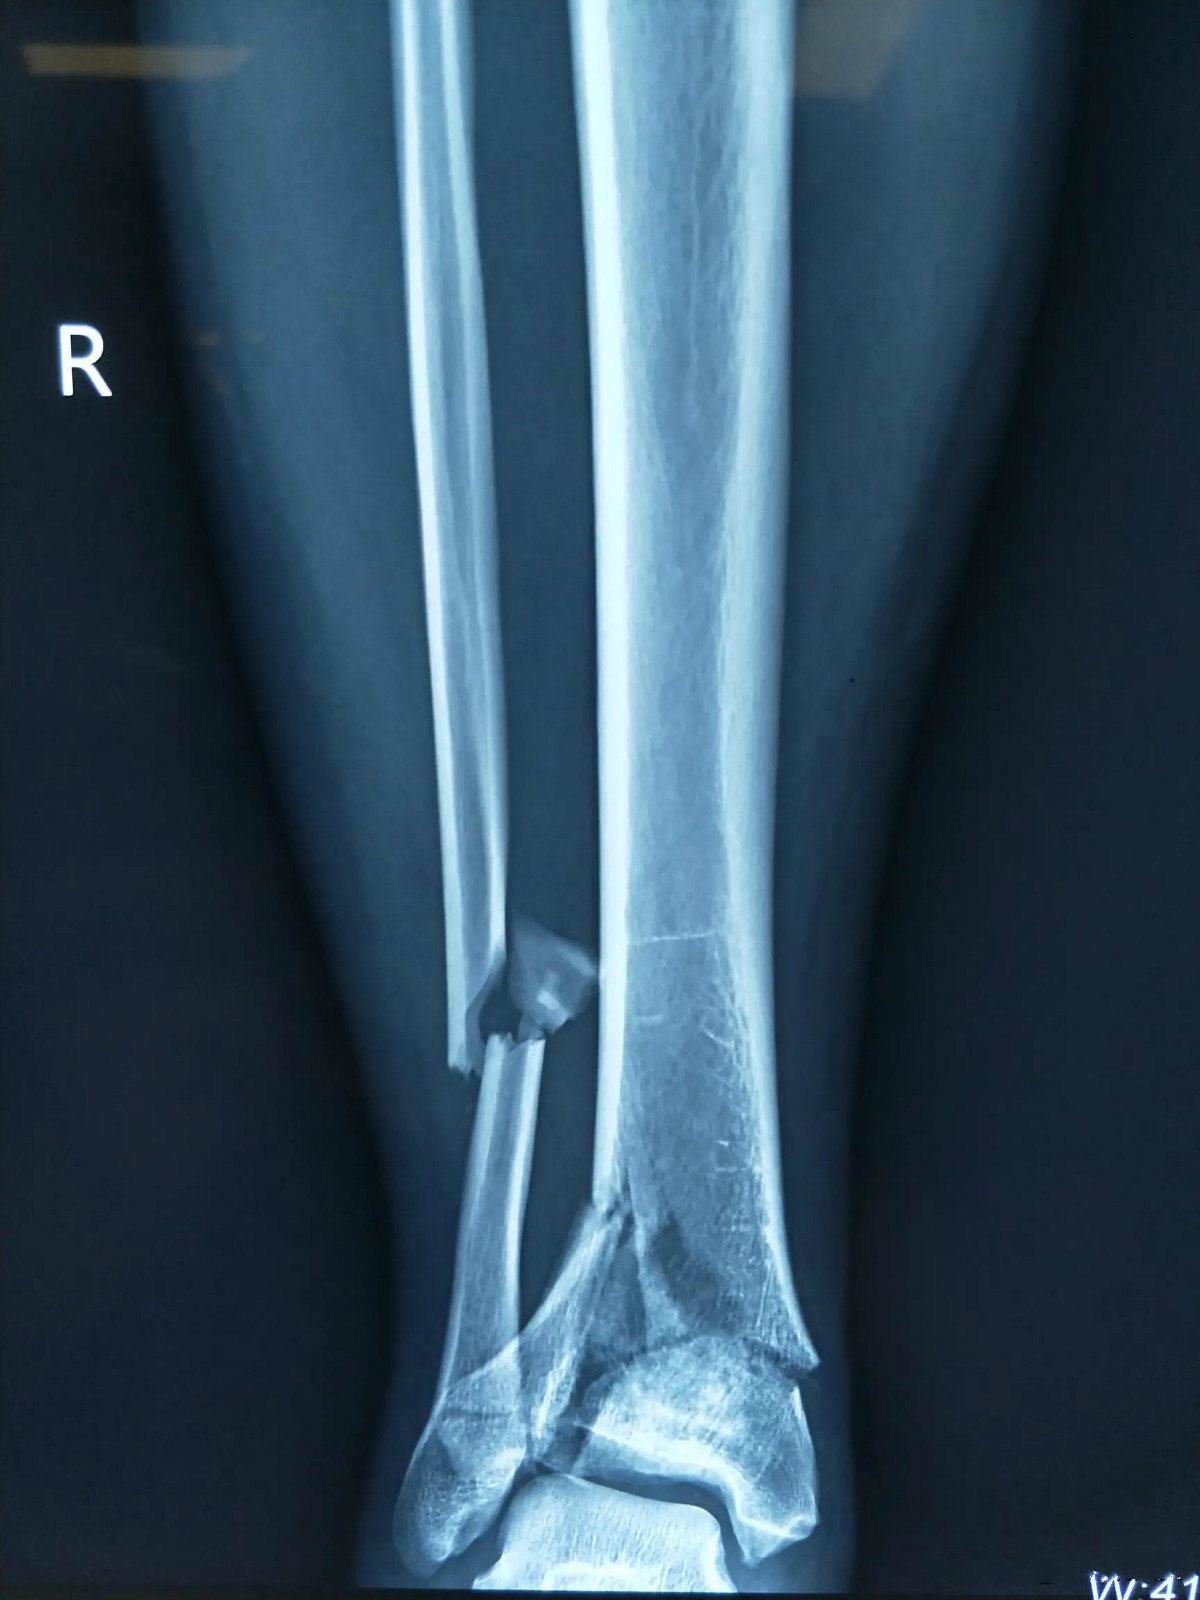

右侧胫腓骨下段骨折

图片尺寸2000x2667